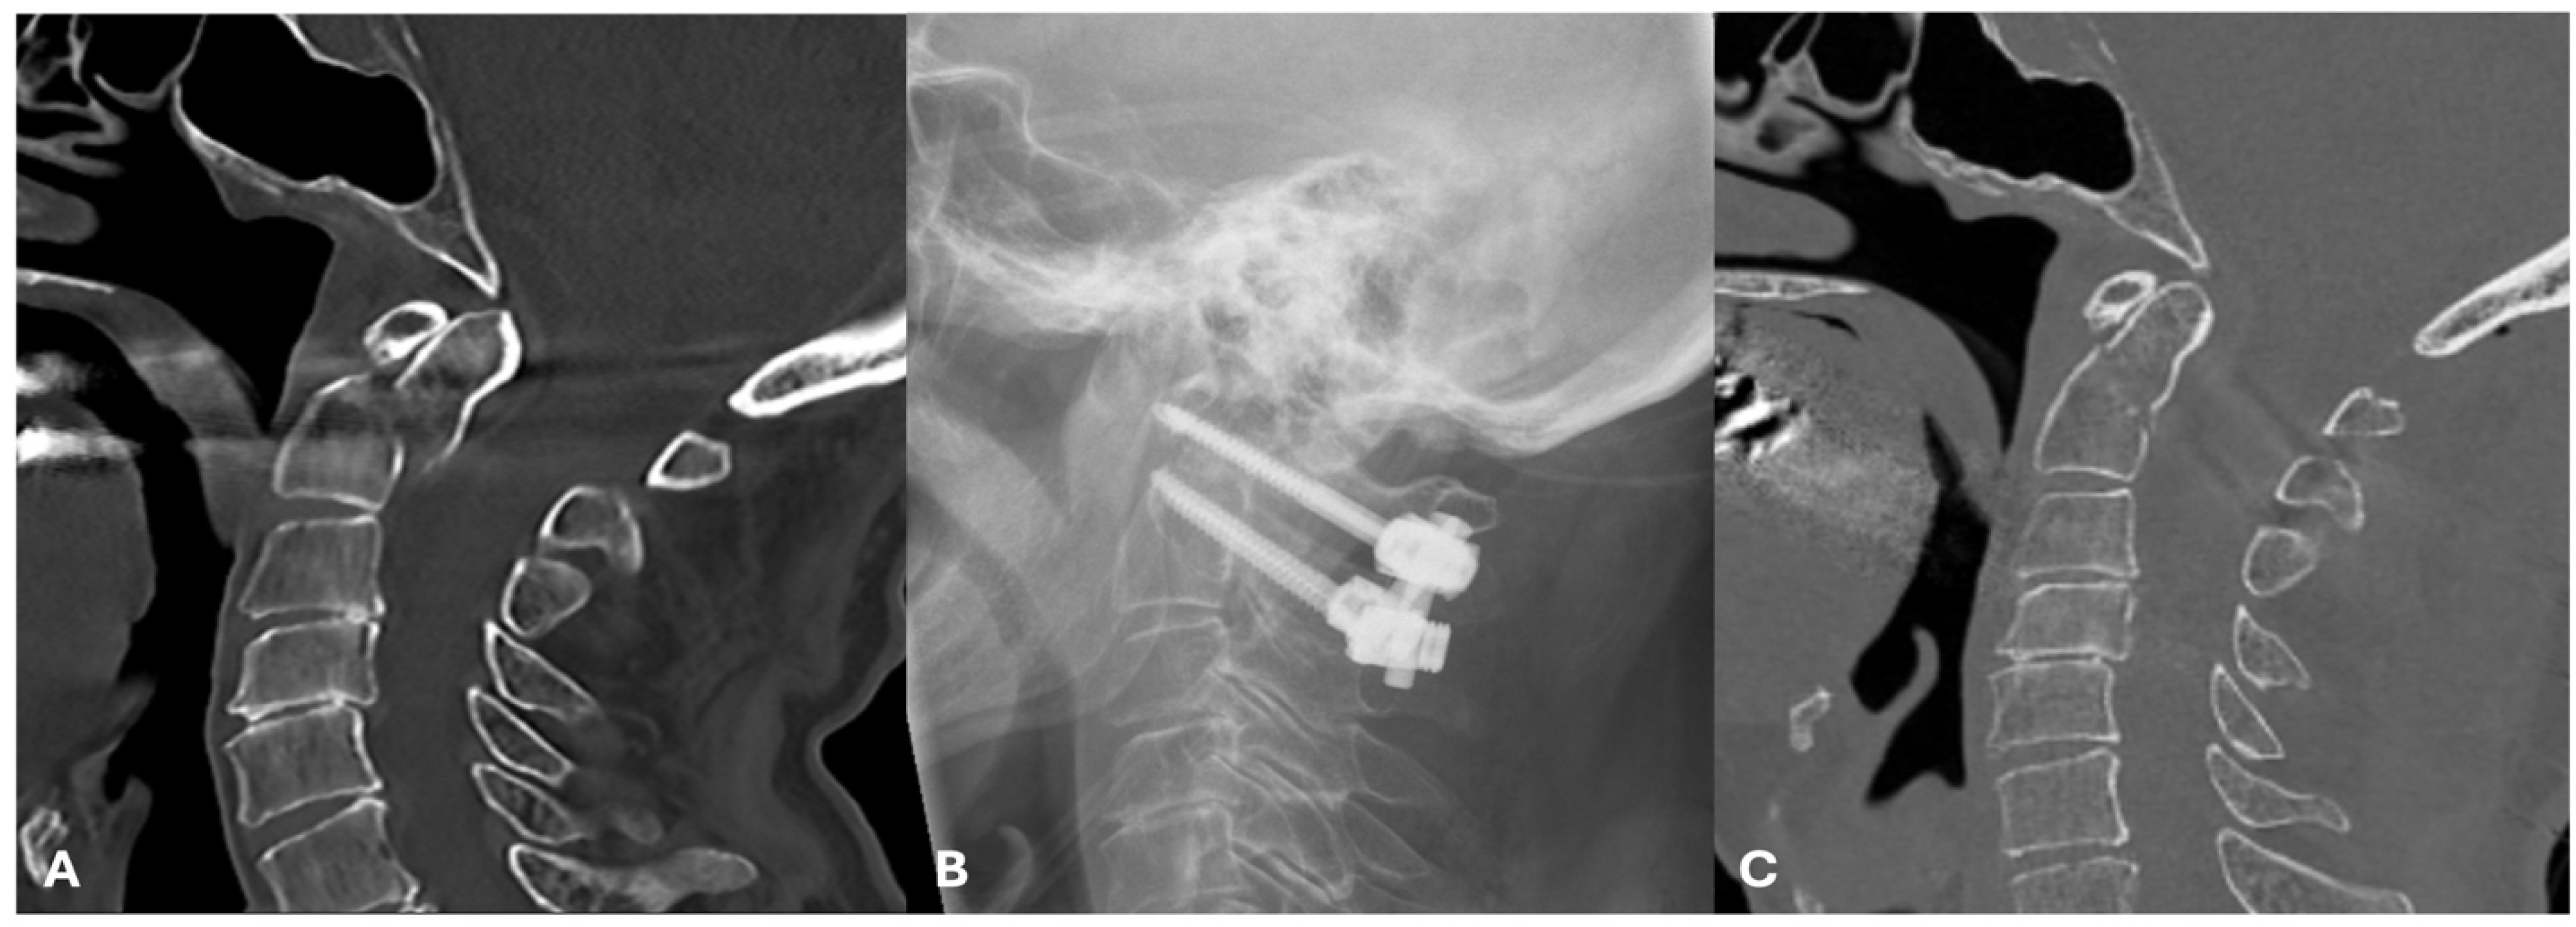

| Odontoid Screw fixation [60] | One or two large odontoid screws are placed caudal–cranially in the direction of the odontoid from an anterior cervical approach. | Type IIA and IIC (Roy-Camille) fractures shown in Figure 1. |